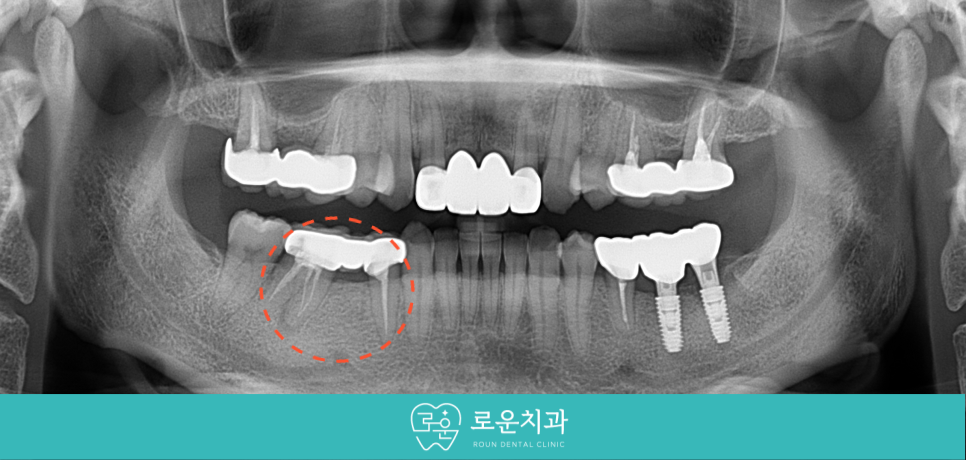

이어 두 번째 작은 어금니(#35)의

재 신경치료를 진행하였는데요.

아래턱 왼쪽 두 번째 큰 어금니(#37) 발치 후

2달쯤 경과하였을 때

임플란트 식립이 가능한 환경이 되었다고 판단하여

식립을 도와드렸습니다.

먼저 기존 보철물 제거 후

상실된 부위에 안정적인 위치와

추후 보철물을 고려하여

정확한 방향으로 임플란트 식립을 진행하였으며,

첫 번째 큰 어금니(#46)의 재 신경치료 후

첫 번째 작은 어금니(#44)와 함께

크라운 수복을 도와드렸습니다.